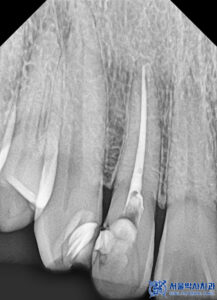

신경치료의 마지막 과정인 근관 충전에서

일반적으로 사용되는 ‘고무 성분’ 대신,

저희 치과는 ‘MTA(바이오세라믹)’를 사용합니다.

MTA는 재료비가 훨씬 비싸지만,

신경치료 후 재감염 가능성을 낮추고

일반적인 신경치료보다 예후가 훨씬 좋기 때문에

서울박사치과에서는 MTA를 고집하고 있습니다.

특히 치아를 살릴 수 있는 모든 가능성을

고려하여 신경치료를 진행하며,

뿌리 하나하나를 정밀하게 찾아 신경을 제거하고

MTA 충전으로 치료의 내구성을 높여 주었습니다.